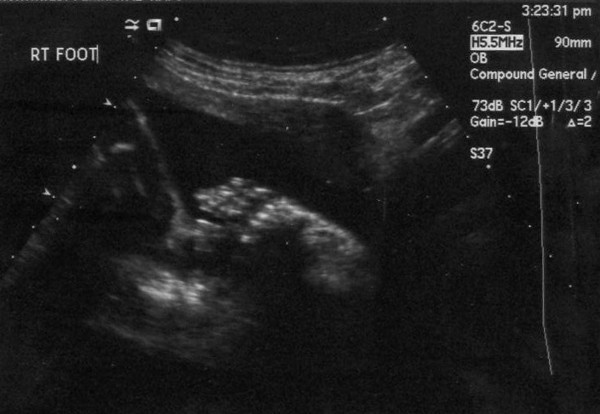

Here is the right foot. All five toes were there. It was rather difficult to get a picture of the left foot for a few reasons, not the least of which being that Junior was moving like crazy.